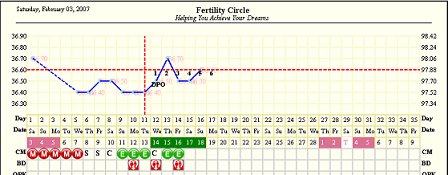

Szezsó, hát ez érdekes. Szerintem vannak tankönyv szerinti esetek és normál pé-k, de szerintem vannak kivételek, nem lehet általánosítani csak így. Nem írtál neki vissza? Lehet, hogy meg kellene írnod neki, mi volt a múlt hónapban, kiváncsi lennék mit válaszol.......